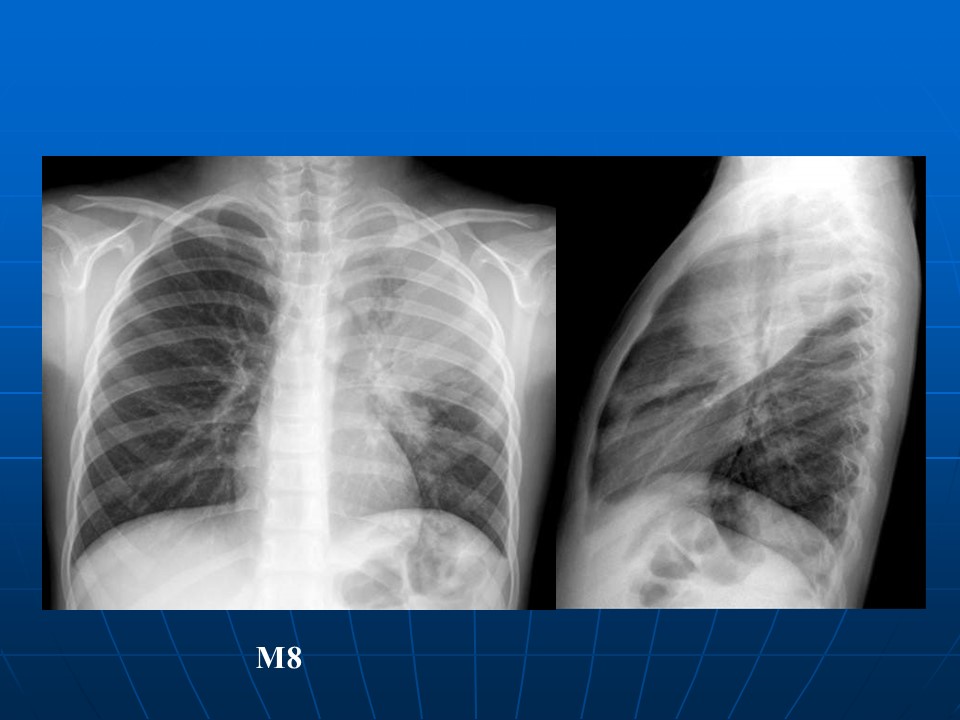

HRCT树芽征的诊断价值